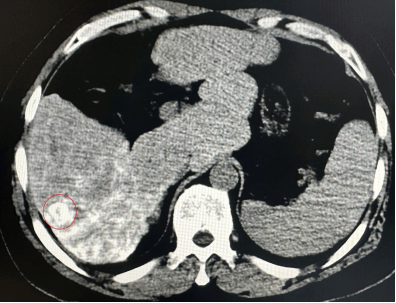

图1 红色圆圈内为肝癌病灶